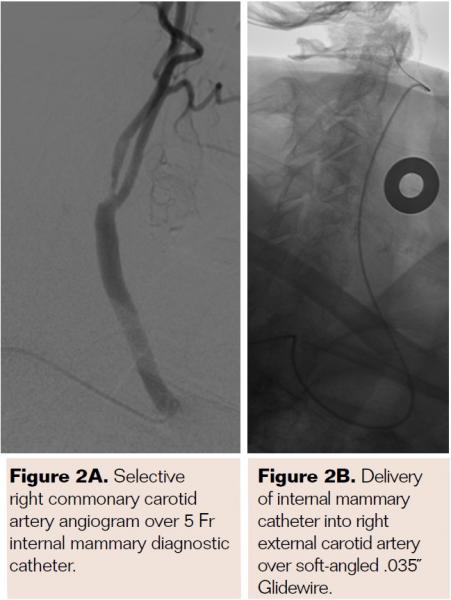

Pretreatment with dual-antiplatelet therapy (DAPT) was started 4 days prior to the procedure with aspirin and clopidogrel, with 600 mg loading dose of clopidogrel and 80 mg dose of atorvastatin the morning of the procedure. The right radial artery was accessed with a 6 Fr Terumo radial sheath, but intraarterial nitroglycerin was not administered due to a prior history of profound hypotension with sublingual nitroglycerin. Verapamil was withheld due to a systolic blood pressure of 130 mm Hg. Both right and left anterior oblique arch aortograms with a 5 Fr straight pigtail catheter demonstrated patency of the proximal great vessels, a type I aortic arch, and a calcified proximal right internal carotid artery (ICA) high-grade stenosis with patent right external carotid artery (ECA). The right common carotid artery (CCA) was selected with 5 Fr internal mammary (IM) diagnostic catheter that confirmed an 85% proximal right ICA stenosis. A soft-angled .035˝ Glidewire (Terumo) was advanced into the right ECA, exchanged out for an Amplatz .035˝ super-stiff wire (Boston Scientific), followed by removal of the diagnostic catheter, and radial sheath. A 6 Fr Shuttle sheath (Cook Medical) was delivered into the distal right CCA. After intracranial angiography, a NAV-6 Emboshield (Abbott Vascular) was deployed in the distal extracranial ICA, followed by predilation with a 4 x 30 mm Trek (Abbott Vascular), and deployment of a 7 x 30 mm Precise self-expanding stent (Cordis). Postdilation was performed with a 5 x 20 mm Maverick NC balloon (Boston Scientific), and then with a 6 x 20 mm Aviator balloon (Cordis) in order to then deliver the retrieval catheter. After repeat angiography confirmed an excellent result, the Shuttle was removed, and hemostasis achieved with TR band (Terumo) (Figures 2A-2R).